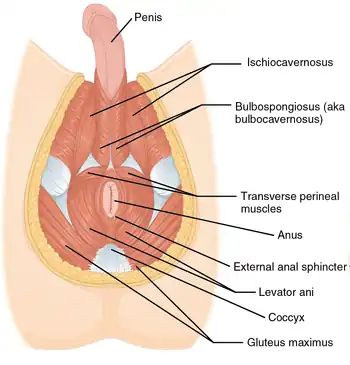

Pelvic floor

The pelvic floor has two inherently conflicting functions: One is to close the pelvic and abdominal cavities and bear the load of the visceral organs; the other is to control the openings of the rectum and urogenital organs that pierce the pelvic floor and make it weaker. To achieve both these tasks, the pelvic floor is composed of several overlapping sheets of muscles and connective tissues.[5]

The pelvic diaphragm is composed of the levator ani and the coccygeus muscle. These arise between the symphysis and the ischial spine and converge on the coccyx and the anococcygeal ligament which spans between the tip of the coccyx and the anal hiatus. This leaves a slit for the anal and urogenital openings. Because of the width of the genital aperture, which is wider in females, a second closing mechanism is required. The urogenital diaphragm consists mainly of the deep transverse perineal which arises from the inferior ischial and pubic rami and extends to the urogenital hiatus. The urogenital diaphragm is reinforced posteriorly by the superficial transverse perineal.[6]

The external anal and urethral sphincters close the anus and the urethra. The former is surrounded by the bulbospongiosus which narrows the vaginal introitus in females and surrounds the corpus spongiosum in males. Ischiocavernosus squeezes blood into the corpus cavernosum penis and clitoridis.[7]